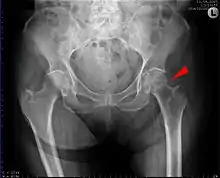

Imaging

Typically, radiographs are taken of the hip from the front (AP view), and side (lateral view). Frog leg views are to be avoided, as they may cause severe pain and further displace the fracture.[5] In situations where a hip fracture is suspected but not obvious on x-ray, an MRI is the next test of choice. If an MRI is not available or the patient can not be placed into the scanner a CT may be used as a substitute. MRI sensitivity for radiographically occult fracture is greater than CT. Bone scan is another useful alternative however substantial drawbacks include decreased sensitivity, early false negative results, and decreased conspicuity of findings due to age related metabolic changes in the elderly.

X-rays of the affected hip usually make the diagnosis obvious; AP (anteroposterior) and lateral views should be obtained.